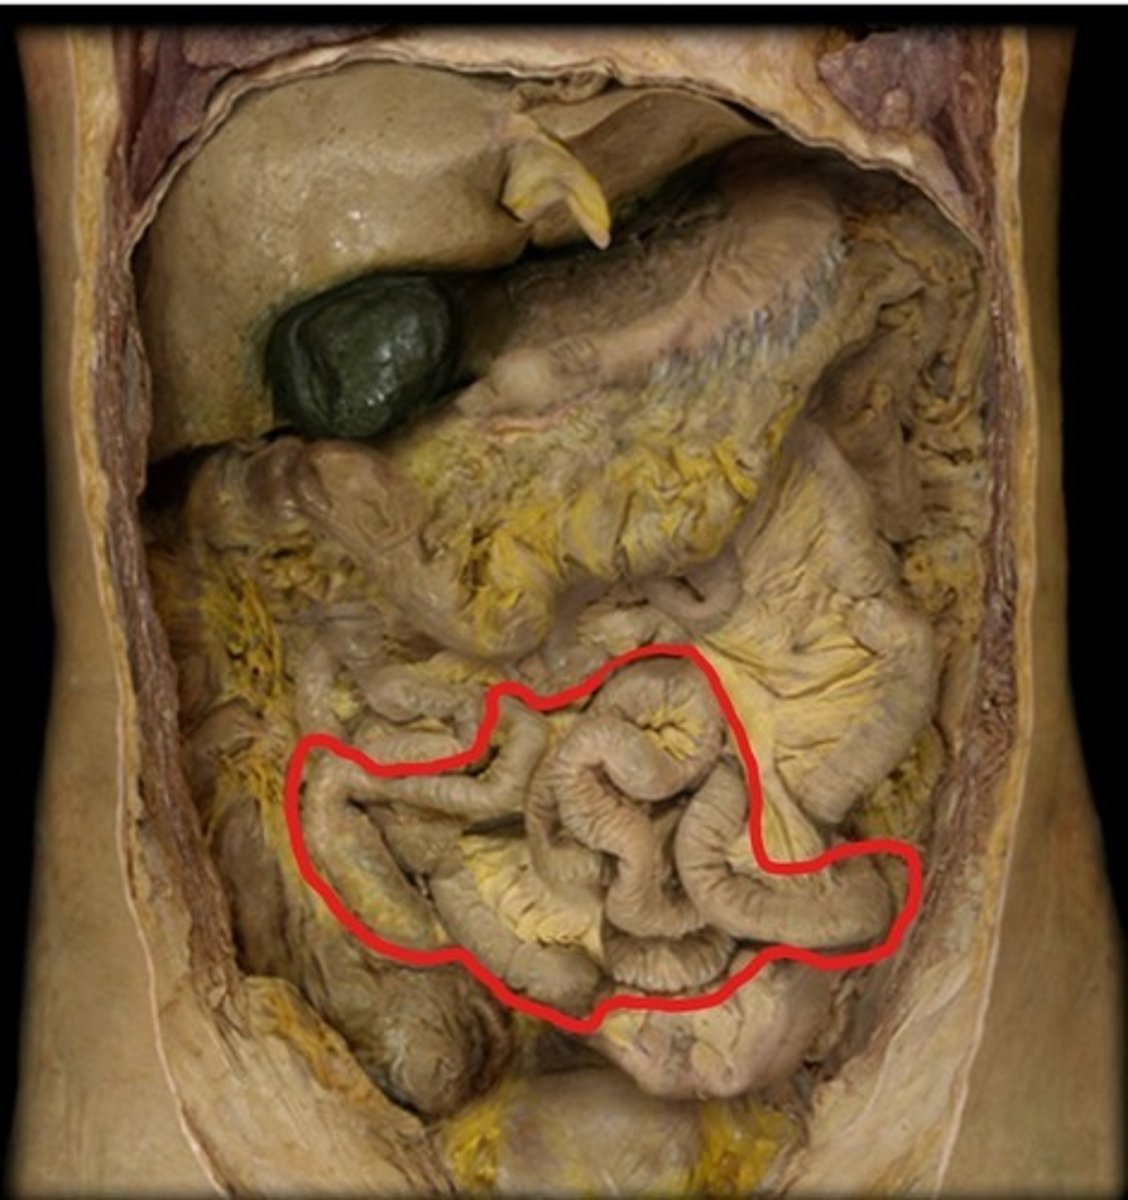

Jejunum

Ileum